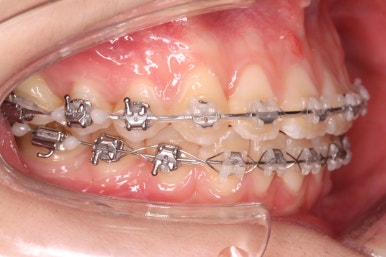

부산교정 키다리아저씨치과에서 장치를 부착하고 교정치료를 시작하였습니다.

이번에 부착한 장치는 엠파워클리어라고 하는 자가결찰 세라믹 장치입니다. 흔히들 클리피씨 장치로 많이 알고 계신 장치가 바로 자가결찰 세라믹 장치인데요.

자가결찰 세라믹 장치 중 또 다른 하나가 엠파워 클리어입니다. 클리피씨는 일본제품, 엠파워 클리어는 미국제품으로 제조회사가 다를 뿐 큰 분류에서는 비슷한 장치라고 보시면 되겠습니다.

부산교정 키다리아저씨치과에서는 이번에 마이크로 임플란트라는 장치를 추가로 사용하였습니다.

잇몸뼈에 교정 치료기간동안 잠깐 사용하는 매우 작은 스크류인데요. 단단히 고정시켜 놓고, 어금니를 당겨오는데 사용합니다.

틈을 줄여주고, 어금니를 당겨오고 중앙선을 맞춰줍니다.